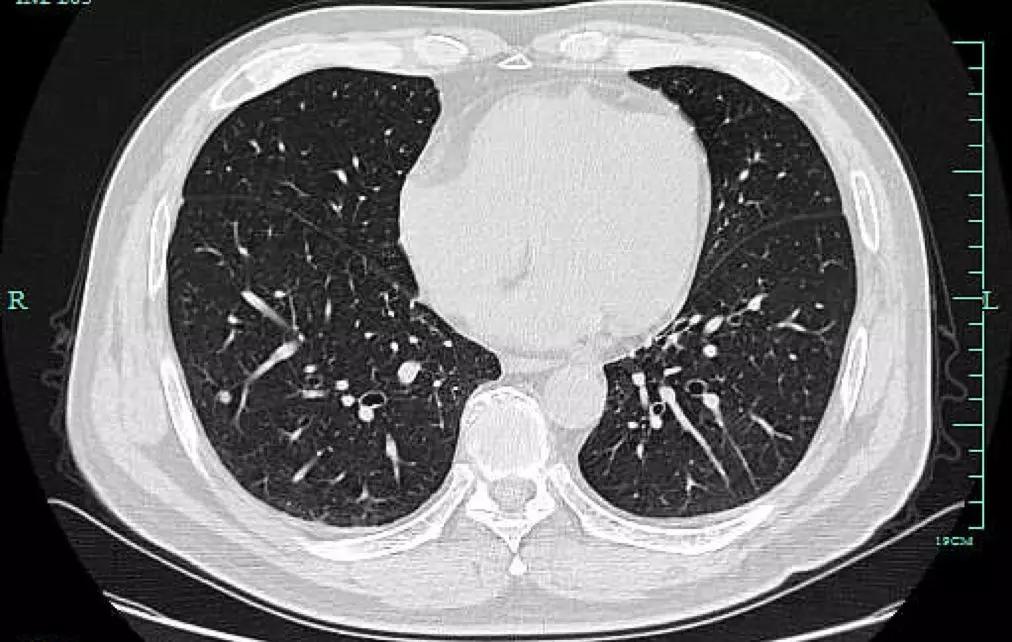

但也许是因为太拼了,章女士忽略了自己的身体变化。前年7月,章女士开始咳嗽,“是那种干咳,也没有流鼻涕没有喉咙痛,应该不是感冒。”她回忆,因为咳得实在难受就想去社区医院配点药,但医生建议她最好去大医院检查一下。章女士便来到浙大一院就诊并预约了检查,拿到体检结果那一刻她却直冒汗,“CT结果说我两侧的肺上都有磨玻璃小结节,右肺上叶的已经有1厘米大了,首先考虑是肺癌,我吓都吓‘死’了。”

肺结节是肺癌筛查中最常发现的类圆形、密度增高的肺部阴影。如果从大小来看,直径小于5毫米的叫做微小结节,直径在5毫米至10毫米的叫做肺小结节,小于3厘米的为肺结节,而如果直径大于3厘米就是肿块了。

磨玻璃样结节

磨玻璃样结节是指肺内密度轻微增加,呈模糊的云雾状,但仍能通过病灶看到其内部血管和支气管纹理,就好像透过磨玻璃观察一样。

实性结节是指肺内圆形或类圆形高密度阴影,在CT下呈现白色的影子,足以掩盖它走行的血管和支气管。实性结节的良恶性较难鉴别,有时候很难光凭一张CT来判断,医生需要充分了解病人的既往病史,比如是否有过肺结核、肺炎、其他肿瘤性疾病等,必要的时候,可以通过PET-CT,肺穿刺,甚至微创手术切除等方式明确诊断。